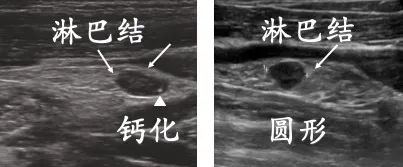

小面积转移的淋巴结长啥样呢?

它们的短边通常小于8毫米

结构基本正常,淋巴结边界也光滑

但左图的淋巴结能在边缘看到微钙化点

右图的淋巴结外形趋圆

做病理能发现

转移灶在2-8毫米之间,没有明显结外侵犯